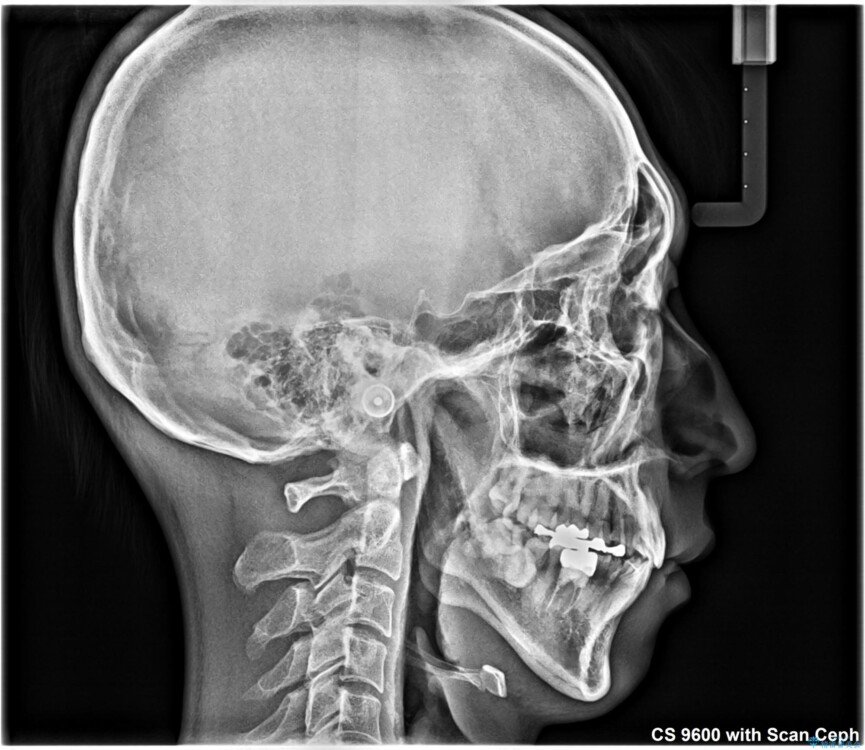

装置は、透明感のあるクリアブラケットとホワイトコーティングされたワイヤーを使用した、目立ちにくい審美装置を選択。

周囲に気づかれにくく、日常生活にも自然に溶け込みます。

治療途中

• 口元の突出感を改善!目立ちにくいワイヤー矯正で自信を持てる自然な横顔に 治療途中画像